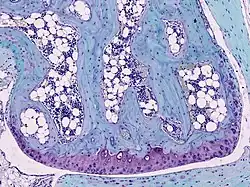

![]() Light micrograph of undecalcified hyaline cartilage showing chondrocytes and organelles, lacunae and matrix. | |

Cartilage is composed of specialized cells called chondrocytes that produce a large amount of collagenous extracellular matrix, abundant ground substance that is rich in proteoglycan and elastin fibers. Cartilage is classified into three types — elastic cartilage, hyaline cartilage, and fibrocartilage — which differ in their relative amounts of collagen and proteoglycan.